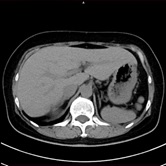

胸部CT 腹部CT

胸部CT画像               腹部CT画像